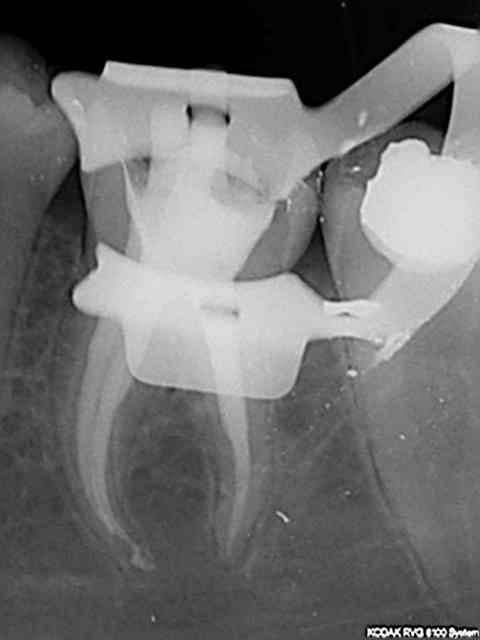

Ayant essayé l'endo express et les protapers le système réciproc est largement devant. ci dessous pulpec 36 effectuée en un temps record, un cas typique ou tu casses un f1 ou f2 protaper.